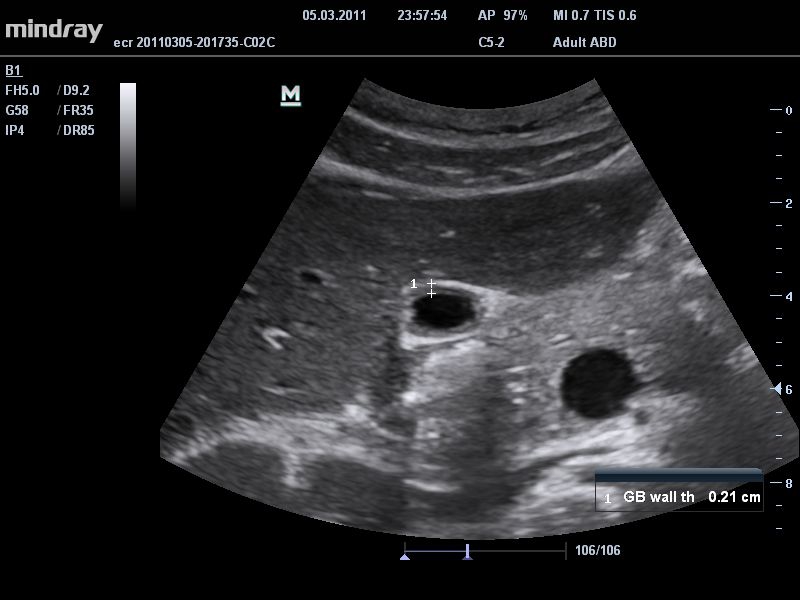

• Технология PSH™: Гармоническая визуализация с фазовым сдвигом для улучшения контрастного разрешения и получения четкого изображения с меньшим уровнем шума.

• Технология iClear™: Автоматическое распознавание структур, обеспечивающее четкие края и контуры, однородное отображение тканей и снижение зернистости в "областях без эхосигнала

• THI со сдвигом фазы: увеличивает четкость визуализации желчного и мочевого пузыря и повышает отношение сигнал-шум.